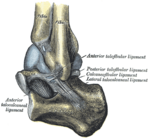

Большеберцовая и малоберцовая кости охватывают блок таранной кости наподобие вилки. Суставная капсула сзади и по бокам прикрепляется к краям сочленяющихся поверхностей, а спереди на полсантиметра отступает от них. Связки располагаются на боковых поверхностях сустава[3]:

• На внешней стороне сустава расположены передняя и задняя таранно-малоберцовые и пяточно-малоберцовая связки — все они расходятся веерообразно, начинаясь на латеральной лодыжке: передняя таранно-малоберцовая связка (лат. ligaméntum talofibuláre antérius) крепится к шейке таранной кости, задняя таранно-малоберцовая связка (лат. ligaméntum talofibuláre postérius) — к заднему отростку таранной кости, а пяточно-малоберцовая связка (лат. ligaméntum calcaneofibuláre) спускается вниз, оканчиваясь на наружной поверхности пяточной кости.

• На внутренней стороне голеностопного сустава расположена дельтовидная (медиальная) связка (лат. ligaméntum deltoídeum seu mediále), которая начинается на внутренней (медиальной) лодыжке и делится на четыре части:

• большеберцово-ладьевидная часть (лат. pars tíbionaviculáre) прикрепляется к ладьевидной кости стопы;

• большеберцово-пяточная (лат. pars tíbiocalcánea) крепится к пяточной кости;

• передняя и задняя большеберцово-таранные части (лат. pártes tíbiotaláres antérior et postérior), прикрепляющиеся к таранной кости.